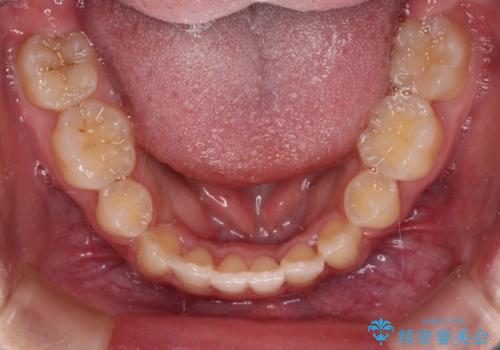

著しい八重歯が気になる インビザラインでの矯正治療

インビザラインでの治療を希望されましたが、インビザライン単独では困難と判断されたため、補助装置や一部ワイヤー装置を用いて行うこととしました。

叢生が強いため、上下左右第一小臼歯4本を抜歯することとしました。

ワイヤー装置を用いた場合、一般的には2年程度で終了することを考えると、「移動量が多くなると治療期間が長くなる」というインビザライン矯正の最大の弱点が現れた治療となりました。